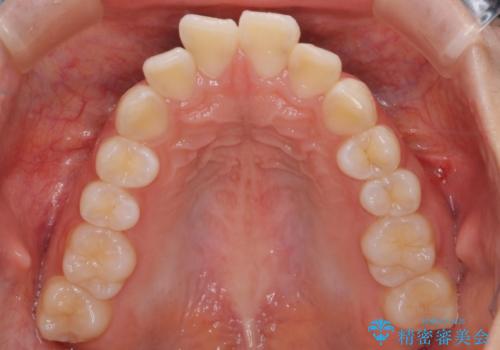

- 前歯のがたつきと口元を気にされて来院されました。

上下4番目の歯を抜歯してがたつきを改善しながら口元を下げる治療計画を立てました。